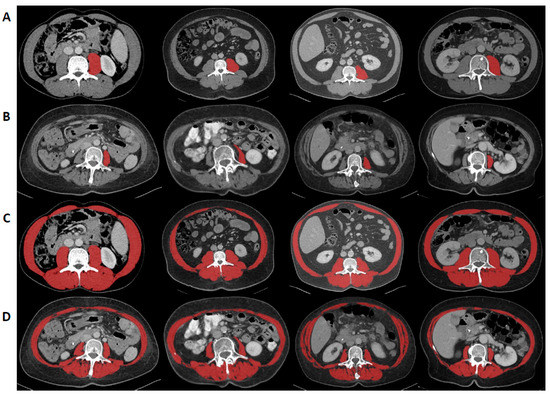

2.2. Analysis of Sarcopenia